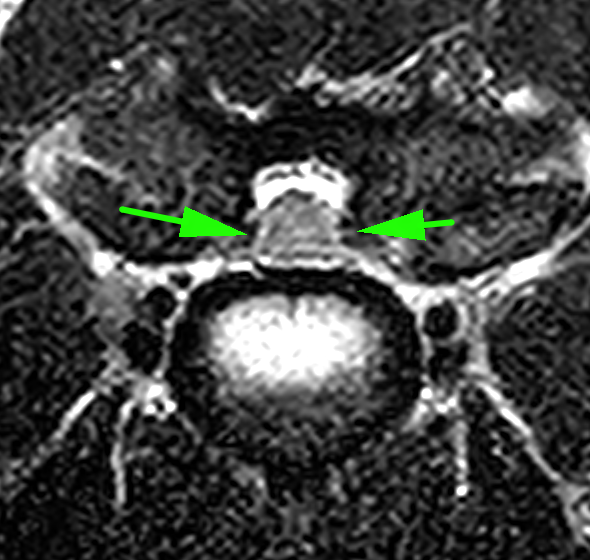

MRI画像検査です。頚椎2−3の圧迫が確認されました。

頚椎3−4での圧迫が確認されました。

椎体中央部の正常な脊髄です。脊髄周囲には脳脊髄液があり、狭窄がないのがわかります。